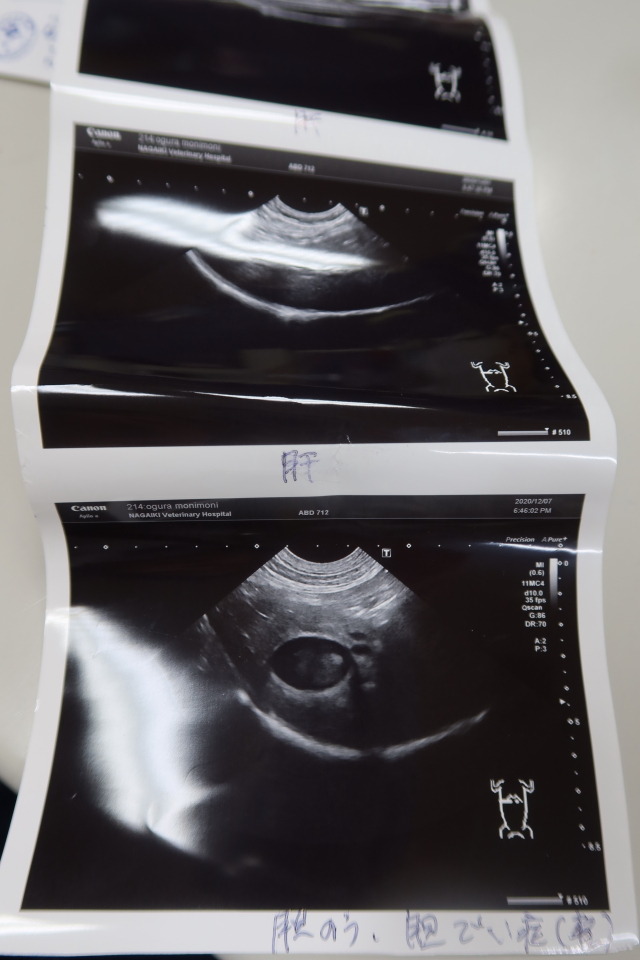

●(生まれて3回目の)エコー。

昨日も、3人で押さえつて、院長がエコーを操作しての計4人がかり。

ちなみにこのエコーの機械、新しくしたばかりの最新の高性能のものだそうです!

【エコー診断の結果】

胆泥があるが(軽度の胆泥症)、先天的なものでわりとあることなので心配なし。

右腎、左腎、脾臓、膀胱、肝臓、副腎大丈夫。